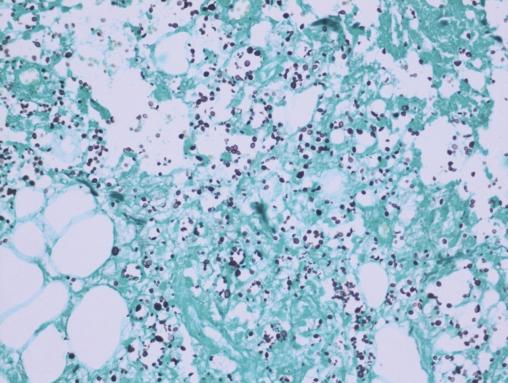

Après quelques jours de traitement immunosuppresseur, une douleur intense et insomniante s’installe, avec érythème et tuméfaction du membre supérieur gauche. Les examens complémentaires retrouvent une protéine C-réactive (CRP) à 300 mg/L, des hémocultures stériles, une échographie Doppler artérioveineuse sans thrombose. Le diagnostic d’une dermohypodermite bactérienne non nécrosante est évoqué dans un premier temps. La patiente est alors traitée par antibiothérapie (amoxicilline et acide clavulanique). L’évolution est défavorable, avec apparition de lésions nécrotico-hémorragiques rapidement extensives (fig. 2 ). Une imagerie par résonance magnétique (IRM) [fig. 3 ] montre une infiltration des parties molles sous-cutanées, des loges musculaires associées à des bulles d’air, en faveur d’une fasciite nécrosante. Une exploration chirurgicale permet de réaliser des biopsies profondes au niveau du fascia et du muscle. Le résultat histologique, après coloration de Grocott, montre une cryptococcose avec multiples foyers de nécrose de liquéfaction (fig. 4 ). Le diagnostic de fasciite nécrosante cryptococcique est finalement retenu. La recherche de l’antigène sérique cryptococique est positive (1 : 2 000, test d’agglutination au latex). La sérologie VIH (virus de l’immunodéficience humaine) est négative. À défaut d’amphotéricine B, du fluconazole à la dose de 400 mg/j est administré. L’évolution a été défavorable, avec décès à la suite d’un choc septique.

Après quelques jours de traitement immunosuppresseur, une douleur intense et insomniante s’installe, avec érythème et tuméfaction du membre supérieur gauche. Les examens complémentaires retrouvent une protéine C-réactive (CRP) à 300 mg/L, des hémocultures stériles, une échographie Doppler artérioveineuse sans thrombose. Le diagnostic d’une dermohypodermite bactérienne non nécrosante est évoqué dans un premier temps. La patiente est alors traitée par antibiothérapie (amoxicilline et acide clavulanique). L’évolution est défavorable, avec apparition de lésions nécrotico-hémorragiques rapidement extensives (